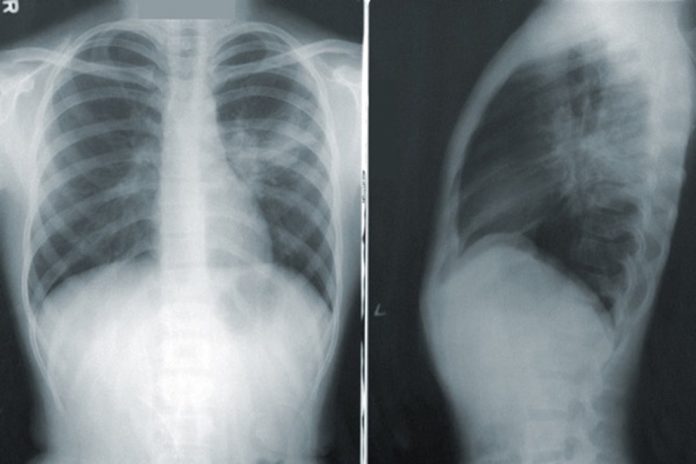

NotiPress.- Ante la llegada de la Covid-19, surgió preocupación por el panorama para pacientes con trastornos respiratorios, como el asma o la enfermedad pulmonar obstructiva crónica (EPOC). Según la Organización mundial de la salud (OMS), en la actualidad hay en el mundo más de dos millones de personas con asma y, en 2016, la prevalencia de la EPOC fue de 251 millones de casos. Para conocer más sobre este tema, NotiPress acudió a un webinar de la empresa de investigación farmacéutica Boehringer Ingelheim y estos fueron los datos más relevantes.

Según el doctor Rafael Hernández Zenteno, neumólogo jefe del servicio de asma y EPOC del Instituto nacional de enfermedades respiratorias (INER), 3.3% de la población padece asma en México. Además señaló, con información del Instituto Nacional de Estadística, Geografía e Informática, que la EPOC y el asma representan la séptima causa de defunción en México. En el mundo, afirmó, la EPOC pasó de ser la sexta causa de muerte, en 1990, a ser la tercera en 2020, de acuerdo a la OMS. En concreto, se refirió a la EPOC como un problema de salud de alta prevalencia, subdiagnosticada y subtratada en etapas tempranas y avanzadas.

En relación con la Covid-19, el doctor Hernández citó un estudio realizado en España donde su ubica a la EPOC como una comorbilidad en menos del 10% de los casos de Covid-19. Mencionó, el escenario es similar para México y que, pese a una tasa de contagios baja en personas con EPOC, los resultados suelen ser severos. También recomendó no suspender los tratamientos de base de las personas con EPOC y asma, pues con esto se ha observado un resultado más benévolo si se contagian. La adherencia al uso correcto del inhalador se relaciona con una redacción de la mortalidad, aunque aún se desconoce la razón de este efecto, señaló.